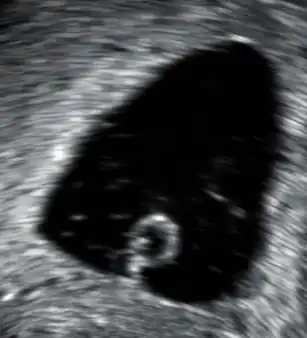

- Aborto retenido: se produce la muerte del embrión o feto, pero se retiene por un tiempo prolongado dentro del cuerpo de la madre. Suelen descubrirse durante los controles prenatales, notándose en la curva de crecimiento uterino la detención de esta y la ausencia de movimientos y latidos fetales.

- Aborto diferido o huevo muerto retenido: el tratamiento definitivamente es la evacuación de la cavidad uterina, pero en este caso primero con misoprostol y luego, si persisten restos retenidos verificados por ecografía transvaginal, se realizará una aspiración manual endouterina o un legrado uterino instrumentado.